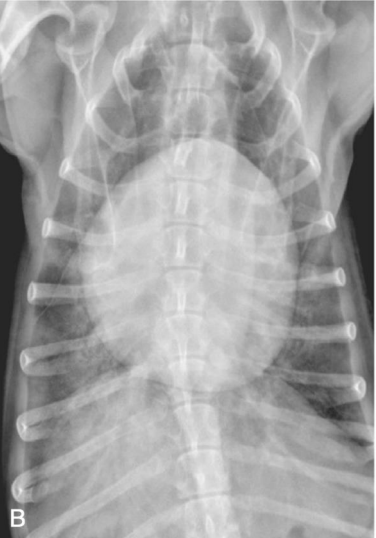

Radiography

• ๋ฐฉ์‚ฌ์„ ์€ ์ตœ๋Œ€ ํก๊ธฐ ๊ธฐ์ค€ (maximal inspiration)

• ํ˜ธํก์ด ๋„ˆ๋ฌด ์•ˆ ์ข‹์œผ๋ฉด ๊ทธ๋ƒฅ DV๋กœ ์—Ž๋“œ๋ ค ์ฐ๊ธฐ๋„ ํ•œ๋‹ค

• ํกํ˜ธ๊ธฐ์— ๋”ฐ๋ผ ์ฐจ์ด๊ฐ€ ์‹ฌํ•˜๋‹ค? ๋น„์ •์ƒ, tracheal collapse๋กœ ์ง„๋‹จ